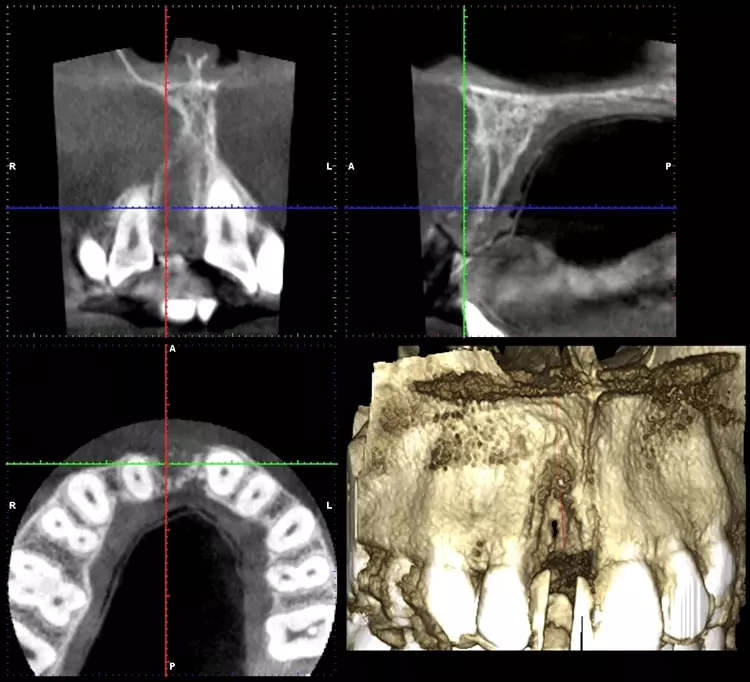

Im Sinne eines Backwardplanning wurde anhand eines Waxups die Marylandbrücke als auch die entsprechende Bohrschablone hergestellt. Nach eingehender präimplantologischer Diagnostik mittels Modellanalyse und digitalem Volumentomogramm (DVT) zeigte sich eine ausgeprägte bukkale knöcherne Fenestration (Abb. 8 und 10).

Nach einer viermonatigen Einheilzeit wurde im Rahmen der präimplantologischen Diagnostik ein DVT zur Überprüfung des Augmentationsergebnisses erstellt und die Implantatgröße festgelegt (Abb. 9 und 11). In Lokalanästhesie und unter Zuhilfenahme einer Bohrschablone erfolgte nach midkrestaler Schnittführung unter Schonung der Papillen die manuelle Insertion eines Straumann Bone Level Implantats mit den Maßen 4,1 x 10 mm RC (Straumann AG, Basel, Schweiz). Das Eindrehmoment betrug 35 Ncm.